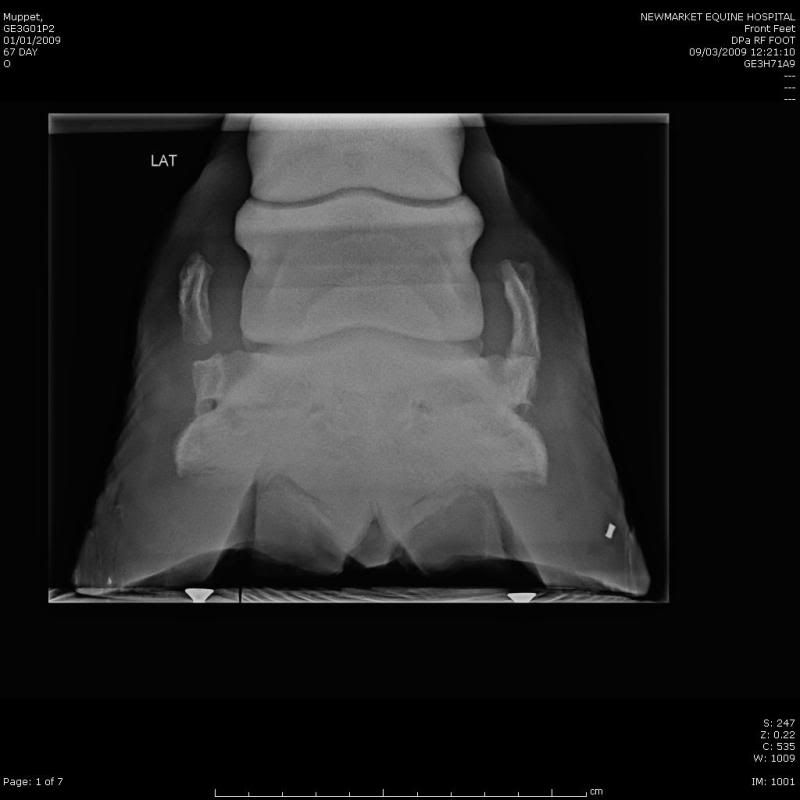

Horse Sidebone X Ray . Can my horse be treated for sidebone? sidebone is hardening of the cartilages on either side of the coffin bone in a horse's hoof. The grades are as follows: Experts aren't sure why these usually springy. There are several methods for grading sidebone lesions, however most literature uses the grading system proposed by ruohoniemi et al. How will i know if my horse has sidebone? despite their similar names and presentations as firm swellings in the pastern region, sidebone and ringbone describe two different and unrelated processes occurring within the horse’s digit. Whilst the sidebone is developing. How can i prevent my horse from developing sidebone?

Horse Sidebone X Ray sidebone is hardening of the cartilages on either side of the coffin bone in a horse's hoof. sidebone is hardening of the cartilages on either side of the coffin bone in a horse's hoof. Can my horse be treated for sidebone? How can i prevent my horse from developing sidebone? How will i know if my horse has sidebone? The grades are as follows: There are several methods for grading sidebone lesions, however most literature uses the grading system proposed by ruohoniemi et al. Whilst the sidebone is developing. despite their similar names and presentations as firm swellings in the pastern region, sidebone and ringbone describe two different and unrelated processes occurring within the horse’s digit. Experts aren't sure why these usually springy.

Radiology To Belvoir Equine Hospital Horse Sidebone X Ray There are several methods for grading sidebone lesions, however most literature uses the grading system proposed by ruohoniemi et al. Can my horse be treated for sidebone? How will i know if my horse has sidebone? The grades are as follows: How can i prevent my horse from developing sidebone? despite their similar names and presentations as firm swellings. Horse Sidebone X Ray.

Radiography, Xray, Foot Horse Side Vet Guide Horse Sidebone X Ray The grades are as follows: sidebone is hardening of the cartilages on either side of the coffin bone in a horse's hoof. There are several methods for grading sidebone lesions, however most literature uses the grading system proposed by ruohoniemi et al. How will i know if my horse has sidebone? How can i prevent my horse from developing. Horse Sidebone X Ray.